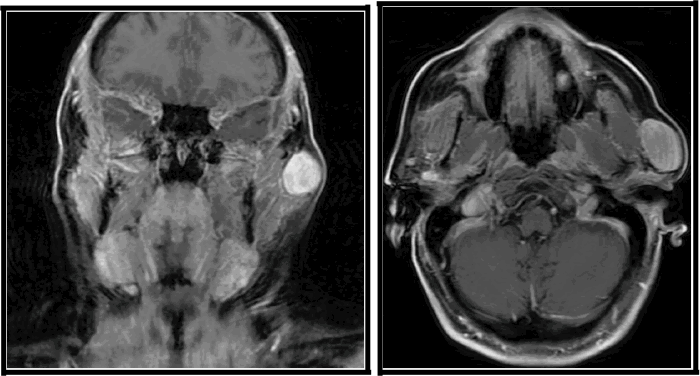

Figure 3. Medium-Power Histopathology Demonstrating Characteristic Features of Solitary Fibrous Tumor. Published with Permission

H&E stain, 20x original magnification illustrating the classic “patternless pattern” of the solitary fibrous tumor. Note the relatively uniform spindle cells, some with an epithelioid appearance, interspersed with prominent, branching, “staghorn” or hemangiopericytoma-like blood vessels, and areas of extravasated red blood cells within a collagenous stroma

Figure 4. High-Power Histopathology of Lesional Cells in Solitary Fibrous Tumor. Published with Permission

H&E stain, 40x original magnification detailing the cytological features of the lesional spindle cells. The cells exhibit ovoid to spindle-shaped nuclei with irregular nuclear membranes and, in some cells, prominent nucleoli. Extravasated red blood cells are scattered throughout the lesion